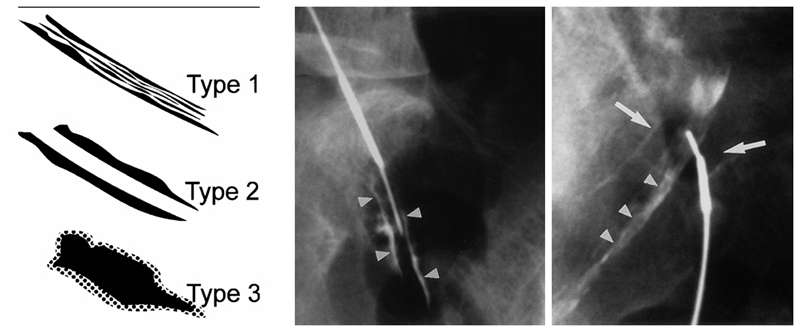

图3

RN入路注射又可分为两种方式,即神经根鞘膜内注射(intra-epineuralinjection)和神经根周围注射(intra-epineuralinjection)。通过造影剂注射可以区分这两种不同的方法,当针尖进入神经根鞘膜内时,会获得神经根内羽毛状神经纤维的显影,而针尖在神经根周围时,造影剂会显示神经根的轮廓。

Pfirrman等对比RN入路两种注射方法的效果认为,尽管两种方法治疗结果相似,但神经根鞘内注射往往会给患者带来严重疼痛,这种注射所带来的疼痛往往已经超出疾病本身的疼痛,因此,神经根鞘内注射是完全没有必要的。

虽然RN入路可以解决注射方法的问题,然而其缺点同样明显,即该方法需要不断试错,在穿刺中,只用穿刺针碰触到病变神经根引起下肢疼痛时,医生才能确定穿刺的成功,因此这种方法具有一定的盲目性,也不可避免的会引起神经根的医源性损伤。